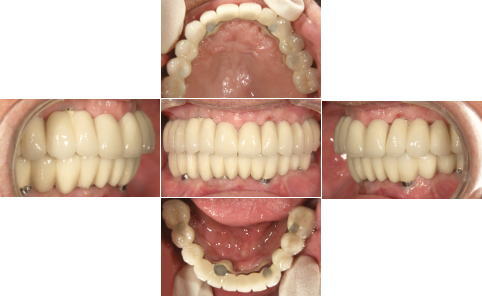

| 治療前 | 治療後 |

| 関西から通っている患者様です。 近々お嬢様の結婚式があるため、その前に上下共、All-on-4で治療して欲しいと来院されました。 右下親知らずは埋伏歯なので残してあります。 |